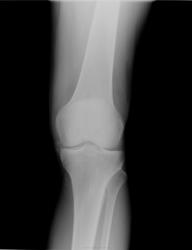

Не знаю, как назвать то, что выступает из суставной щели.

Ну, какие-то клинико-анамнестические данные есть?Может быть это как-то облегчит ситуацию с оценкой скиологии?имхо: в области внутреннего края суставной площадки большеберцовой кости, впечателие о краевой узурации (проявления артирта?)+ плотные парартикулярные включения в мягких тканях по задне-внутренней поверхности сустава. Не исключал бы версию подагического артрита, но представленные клинико-лабораторные данные до неприличия скудны...

На обизвествленый мениск похоже

Да, может оказаться и это.Возможно, что бы расставить точки над i, потребуется МРТ коленного сустава, но начать можно с простого и доступного, жалобы, анамез заболевания, клинико-лабораторные данные, иначе "...наугад, как ночью по тайге".

Нет у меня анамнеза и клин. данных.Пациент "со стороны" муниципальной поликлиники.На направлении "гонартроз".

Написал про обызвествлённый мениск,показал нашему травмоортопеду-он согласился.